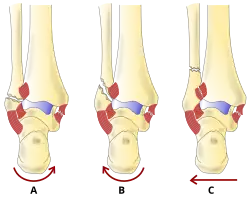

Gegenwärtig werden die Brüche für die operative Versorgung bevorzugt anatomisch nach Danis oder abgeleitet nach Weber[2] eingeteilt, und zwar abhängig von der Höhe des Wadenbeinbruchs im Verhältnis zur bindegewebigen Verbindung zwischen Waden- und Schienbein (Syndesmose). Diese Einteilung wurde von der Arbeitsgemeinschaft für Osteosynthesefragen (AO) in ihre Klassifikation übernommen und weiter differenziert:

| Typ | Frakturlokalisation | Syndesmosenverletzung |

|---|---|---|

| A | Fraktur unterhalb der Syndesmose | Syndesmose immer intakt |

| B | Fraktur auf Höhe der Syndesmose | Syndesmose häufig mitverletzt |

| C | Fraktur oberhalb der Syndesmose | Syndesmose immer mitverletzt |

Das Ausmaß der Gelenkschädigung steigt von A bis C an. Begleitverletzungen wie Innenknöchelbruch und hinteres Schienbeinkantenfragment (Volkmann’sches Dreieck) können das Ausmaß der Gelenkschädigung erhöhen.

Diese Einteilung bezieht sich ausschließlich auf die örtliche Lage des Wadenbeinbruchs. Aus der Zuordnung lässt sich annähernd auf die zu erwartende begleitende Läsion der gabelstützenden Bänder der Syndesmosen-Region und der Membrana interossea schließen.